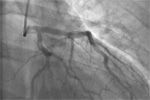

Broad spectrum antibiotic therapy was initiated pending a specific plan. After 3 weeks of treatment, CT angiography (CTA) revealed pancreatic pseudoaneurysms, which were treated with coil embolization. The day after this procedure, the patient experienced tachycardia and sudden abdominal pain without chest pain or dyspnea. An emergency ECG (Figure 4)showed ST segment elevations in the anterolateral leads that had not been seen on ECG at admission (Figure 5). Troponin level was 0.37 ng/mL and findings of a repeat abdominal CT scan were negative for any acute pathology. Electrolyte levels were normal. Cardiologists suspected ST-elevation myocardial infarction and proceeded with an emergency catheterization. Angiogram results showed a normal left ventricular ejection fraction without coronary artery disease (CAD) (Figures 6, 7). The catheterization report mentioned minor distal apical arterial malformations (Figure 8). A ventriculogram showed no wall motion abnormalities. A repeat troponin level measured 0.31 ng/mL, a modest, nonspecific elevation. ECG findings 3 weeks later (6 weeks after admission) showed normalization of ST segments (Figure 9).

Left coronary artery; no evidence of CAD Figure 7

Right coronary artery; no evidence of CAD